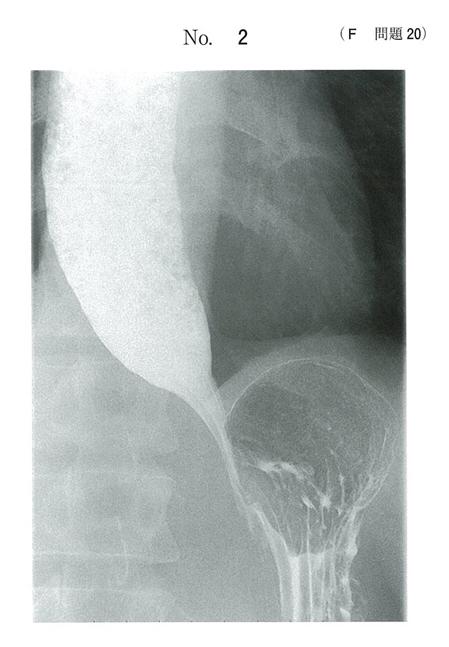

40歳の女性。嚥下困難と嘔吐とを主訴に来院した。35歳を過ぎた頃から前胸部に食物のつかえを感じるようになった。1年前から食物がつかえたときにお茶で流しこむことが月に2回程度あった。最近、食後に嘔吐するようになったため受診した。吐物はほとんど飲み込んだ食物であり体重減少はない。上部消化管造影像(別冊No.2)を別に示す。

考えられるのはどれか

a 食道癌

b 食道憩室

c 逆流性食道炎

d 食道アカラシア

e 食道裂孔ヘルニア